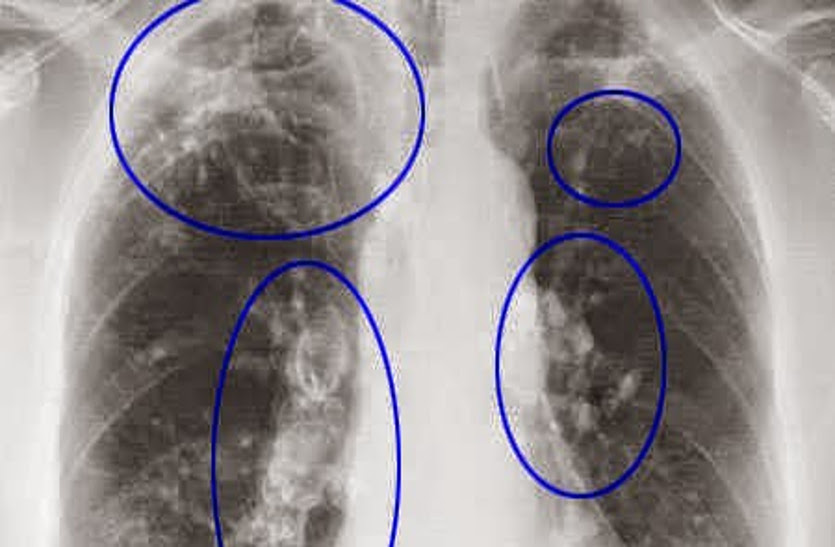

सिलिकोसिस मुख्यतया पत्थर खदानों में होती है। सिलिकायुक्त धूल में लगातार सांस लेने से फेफड़ों में होने वाली बीमारी को सिलिकोसिस कहा जाता है। पत्थरों की घिसाई करने वाले कारीगर, श्रमिक और खदानों में पत्थर निकालने वाले श्रमिक इसके अधिक शिकार होते हैं। इसमें मरीज के फेफड़े बेकार हो जाते हैं।